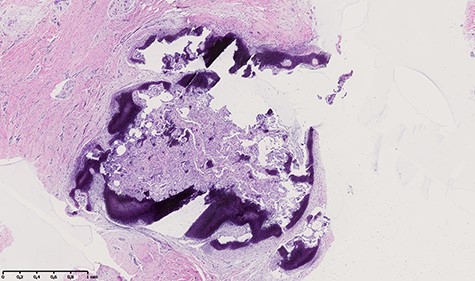

An en-bloc resection of the dorsal part of the phalangeal tuft was performed (Fig. 5). The histological examination described a nodule measuring 3 × 2mm, containing an immature osteoid matrix, bordered by osteoclast with many prominent vessels, and surrounded by peripheral osteosclerosis (Fig. 6). This image evoked a nidus and confirmed the diagnosis of OO. The wound healed uneventfully. The pain at the pressure disappeared completely after the operation and no recurrence was observed after 1 year.

Histologic appearance showing a nodule measuring 3 × 2 mm, containing an immature osteoid matrix, bordered by osteoclast with many prominent vessels, and surrounded by peripheral osteosclerosis.